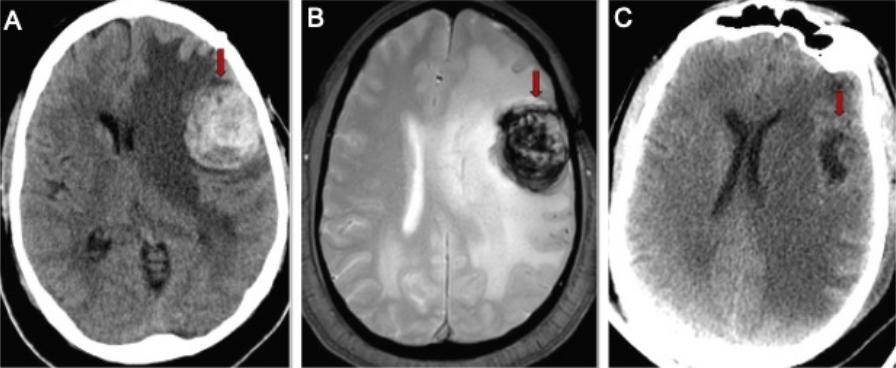

Direct removal of the cavernous malformation with surgery is the only known cure. Surgery is often recommended for cavernous malformations that are causing symptoms, grow on repeat imaging and can be removed with low risk of harming the surrounding brain (Figure 2).

Cavernous malformations are surgically removed under general anesthesia in the operating room. The neurosurgeon locates the correct area of the brain using an intra-operative GPS system called stereotactic navigation. A small pathway is made through the bone over the malformation. The navigation system is used to pinpoint the lesion and the malformation is meticulously removed using an operative microscope. The goal is complete removal of the cavernous malformation with minimal disruption of surrounding brain tissue.

Figure 3. A. Brain CT scan in a patient having difficulty speaking shows a 3cm mass containing blood (red arrow). B. Brain MRI showing the mass with blood inside (red arrow). C. CT scan of the brain after surgery showing the cavernous malformation removed (red arrow) and less brain shift.

Surgery for cavernous malformations is best performed at specialized cerebrovascular centers like UCLA Ronald Reagan Medical Center where there are specially trained neurosurgeons, neuro-anesthesia and care in a specialized neurological intensive care unit. Patients are typically in the hospital for two to three days after surgery and length of recovery depends on the individual patient’s cavernous malformation.